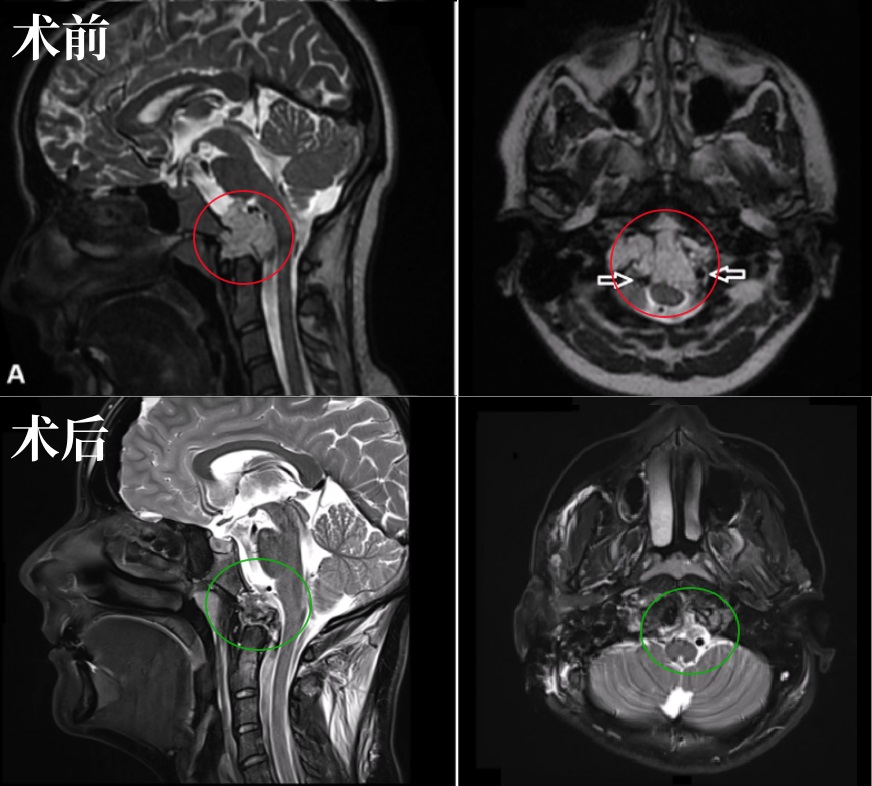

6岁男孩较大脊索瘤单、鼻孔8mm切口、不开颅成功手术

26岁男士较大颅颈交界区脊索瘤压迫脑干,福教授双镜联合全切巨型脊索瘤

21岁女性颅颈交界区脊索瘤